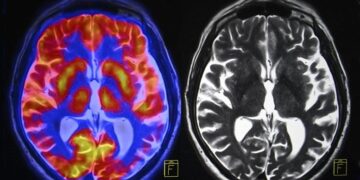

Failing kidneys could also be quietly sending poisonous indicators that harm the guts. Scientists have recognized a key motive why greater than half of individuals with persistent kidney...